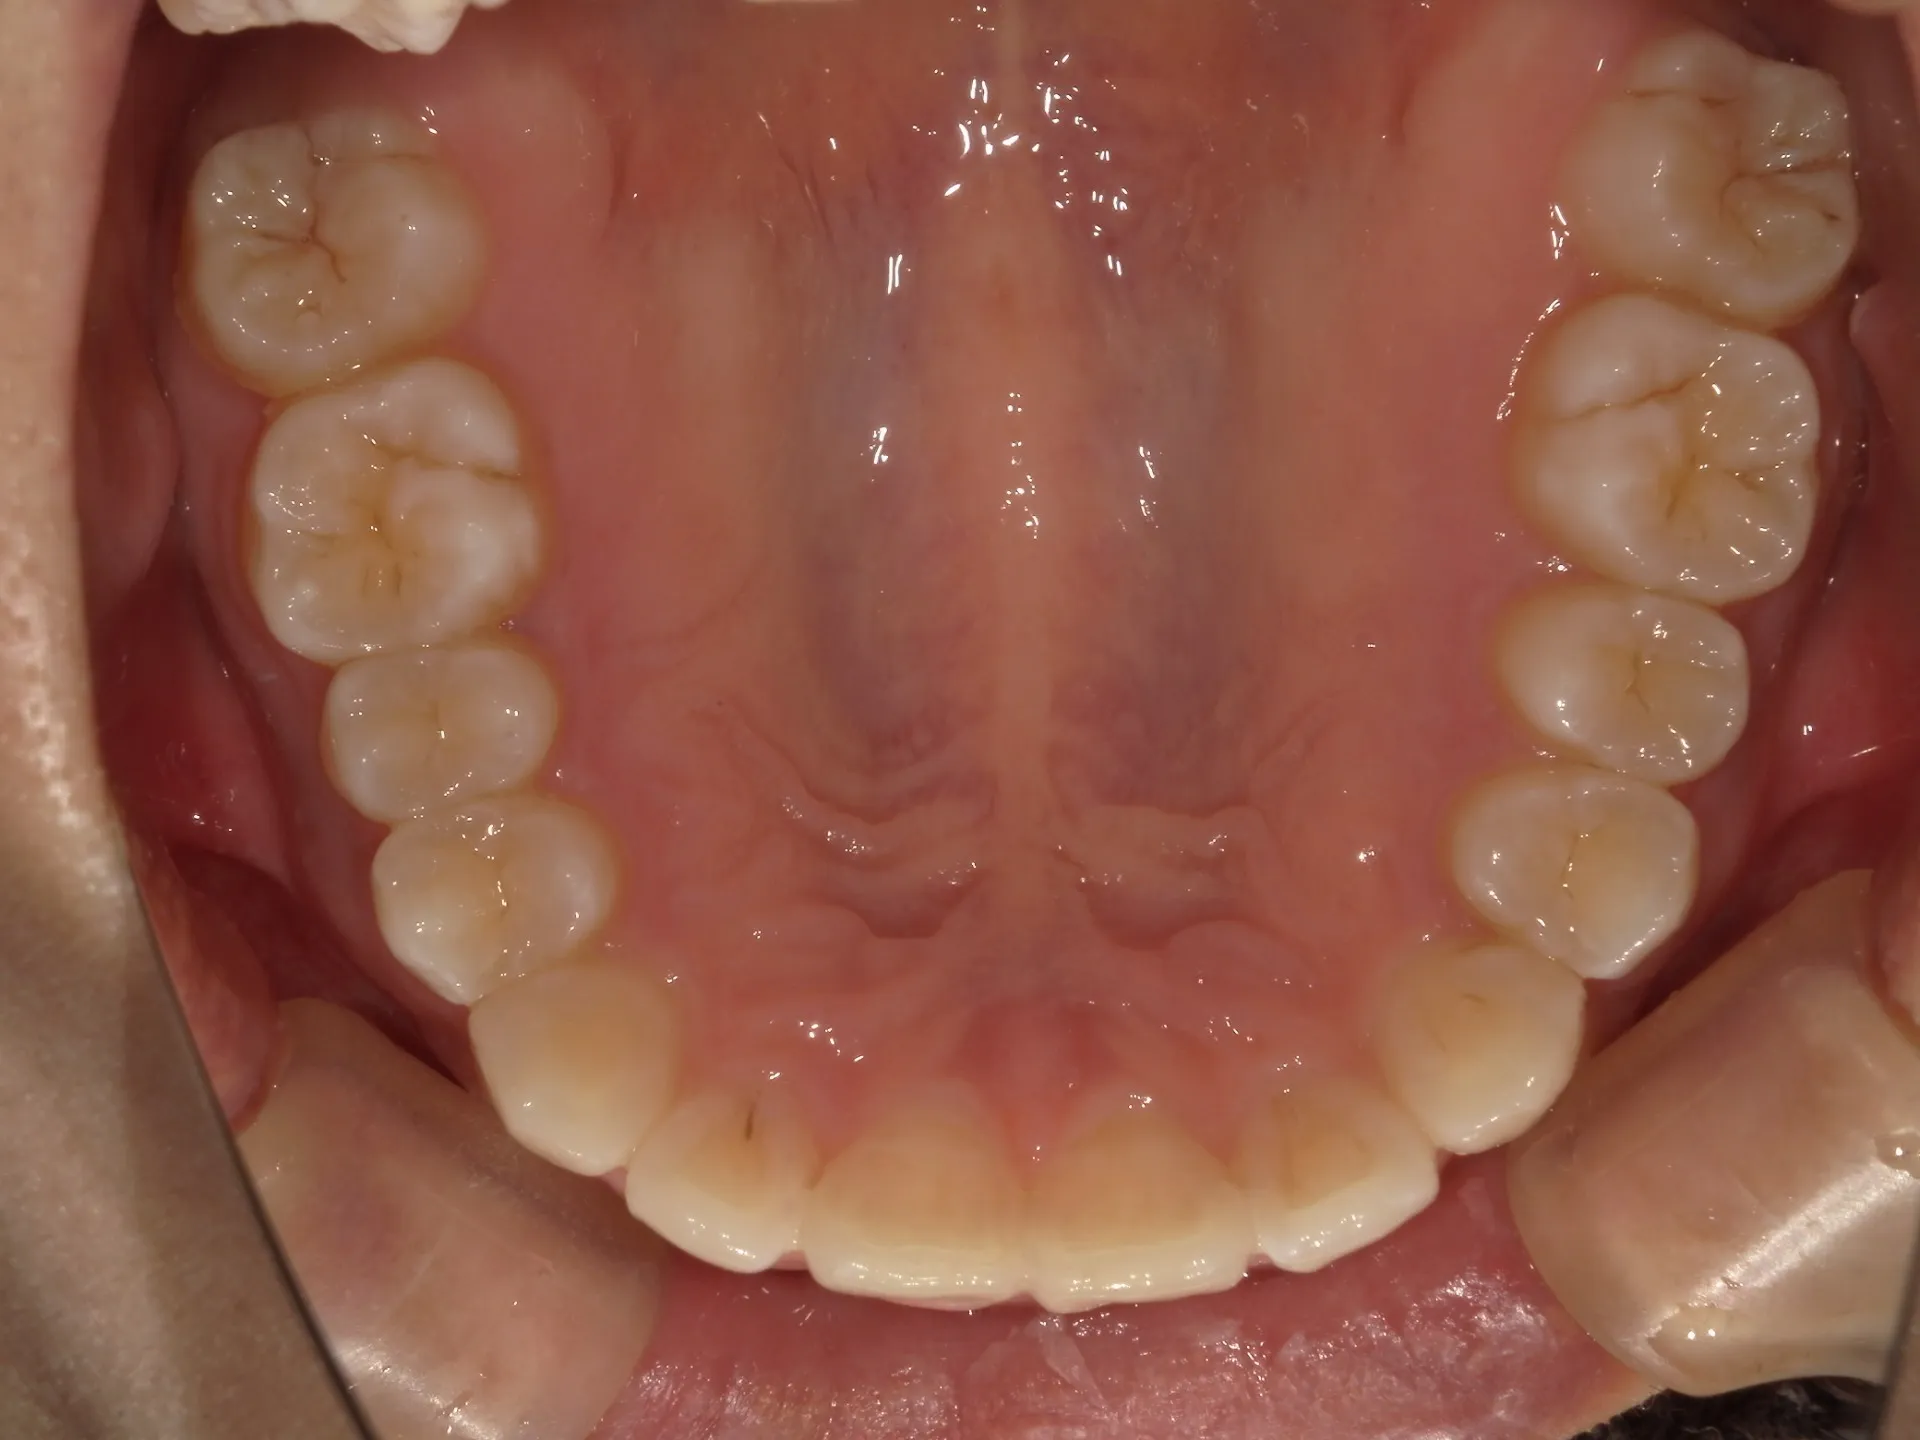

前歯が内側に倒れてたりしませんか?

または2番目の歯が外側に飛び出していませんか?

この2つはよく同時に起こることがあります。

今回はインビザライン矯正治療(マウスピース矯正)で治療した症例についてご紹介いたします。